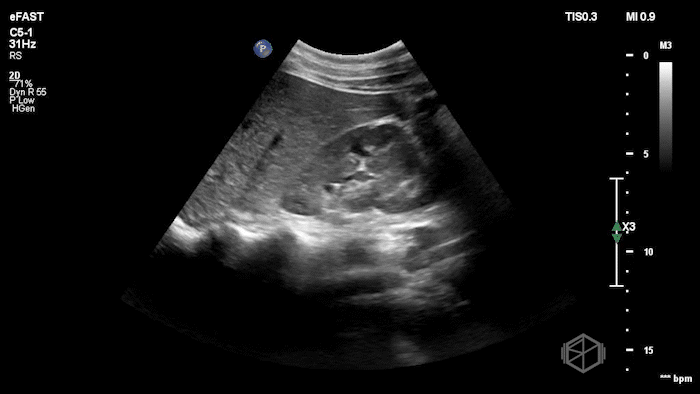

Drs. Ariz and Scavelli were caring for an approximately 40-year-old woman, G2P1, at approximately 8 weeks gestation, who presented to the ED with abdominal cramping. She was hypotensive on arrival, prompting the team to reach for the ultrasound immediately. They saw the following:

POCUS showed free fluid throughout the abdomen, including the RUQ, LUQ, and pelvis. The uterus was empty, and the final clip appears to show a complex left adnexal mass.

Diagnosis: Left ectopic pregnancy with hemoperitoneum